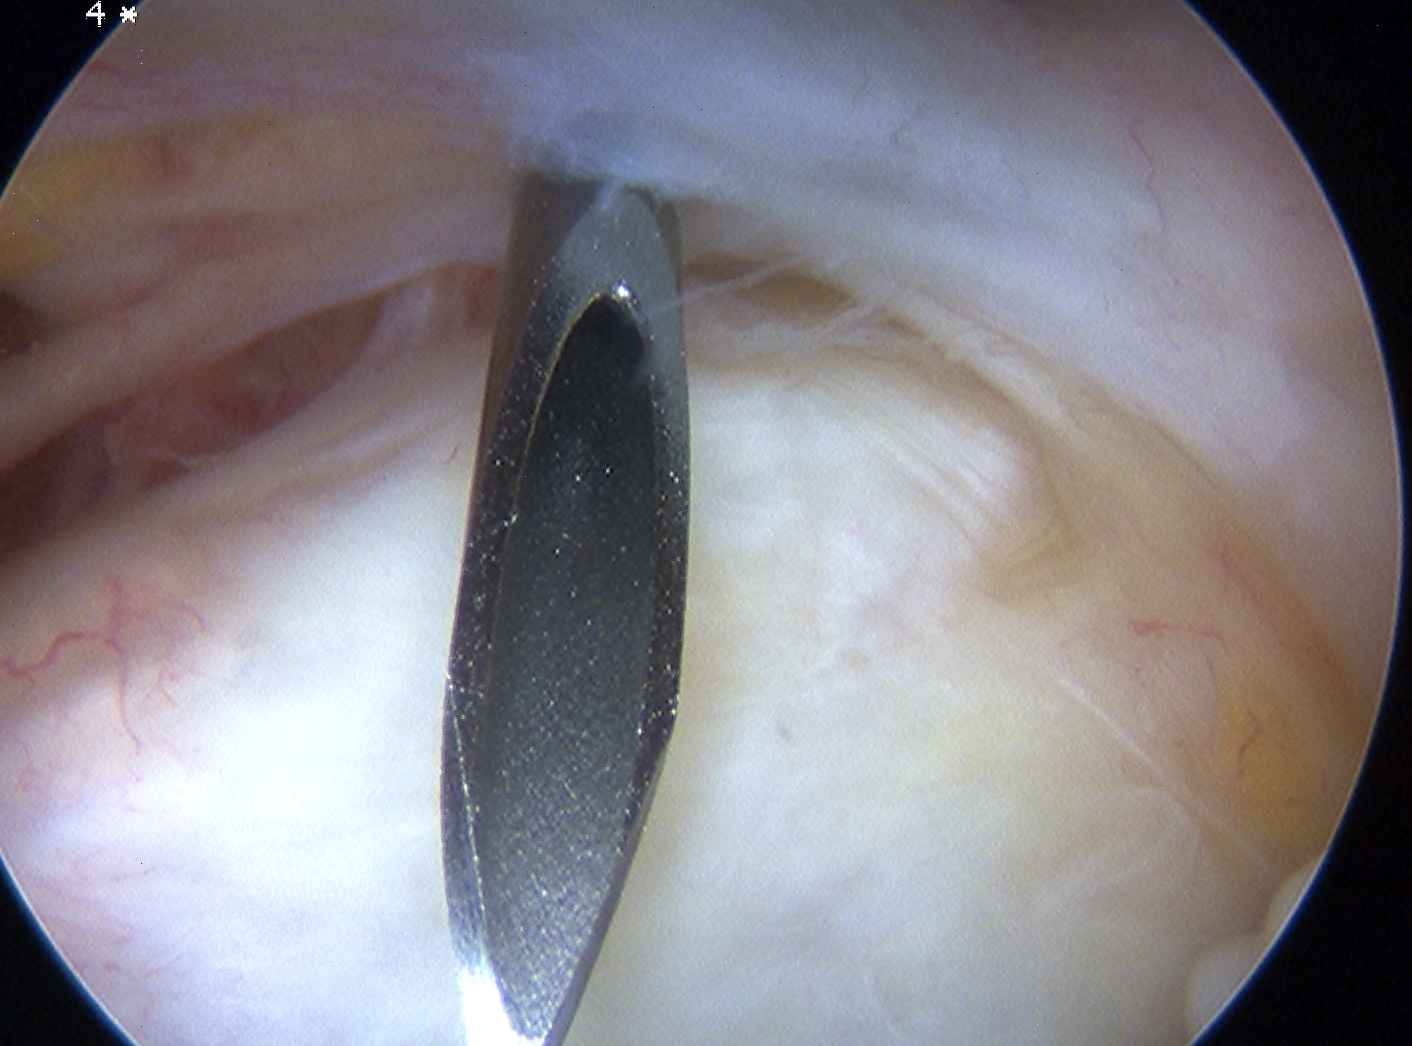

Anterior elbow arthroscopy

Camera in anteromedial portal creating working anterolateral portal

Posterior elbow arthroscopy